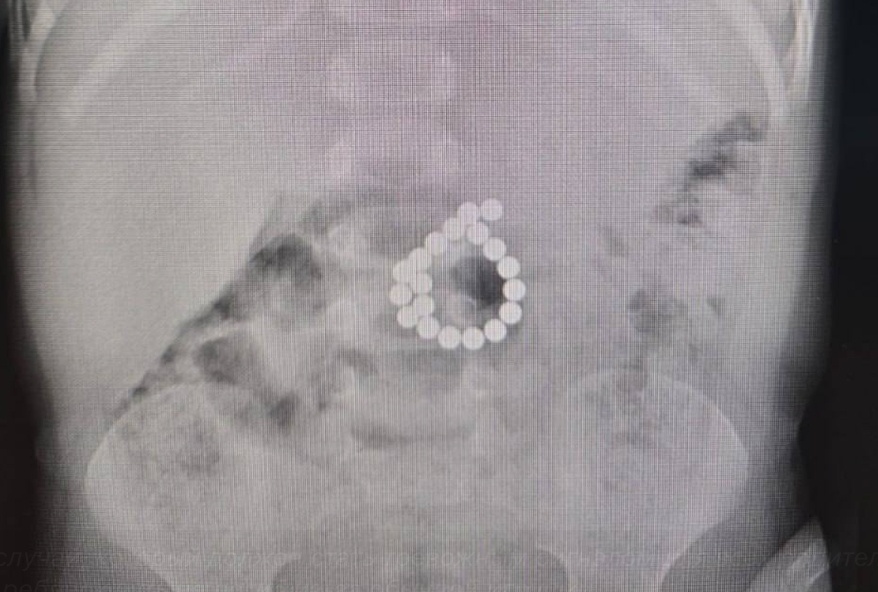

В ходе экстренной операции хирурги обнаружили в толстой кишке ребенка 19 магнитов и двойную перфорацию. Инородные тела были удалены, поврежденные участки ушиты. После оперативного вмешательства ребенок провел 6 суток в реанимации, где получал интенсивную терапию, парентераль

В ходе экстренной операции хирурги обнаружили в толстой кишке ребенка 19 магнитов и двойную перфорацию. Инородные тела были удалены, поврежденные участки ушиты. После оперативного вмешательства ребенок провел 6 суток в реанимации, где получал интенсивную терапию, парентеральное питание, антибиотики и обезболивание.